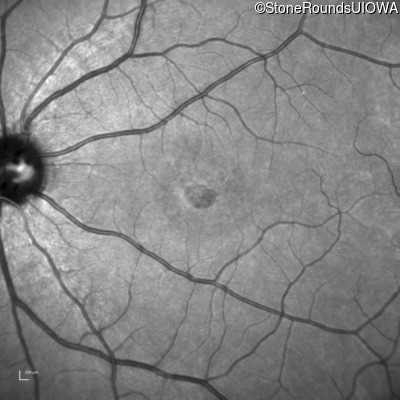

Age at visit: 17 years

OD OS

This 17 year old female first noted problems with her visual acuity around age 13 when she had trouble seeing the projector from the back of the classroom.